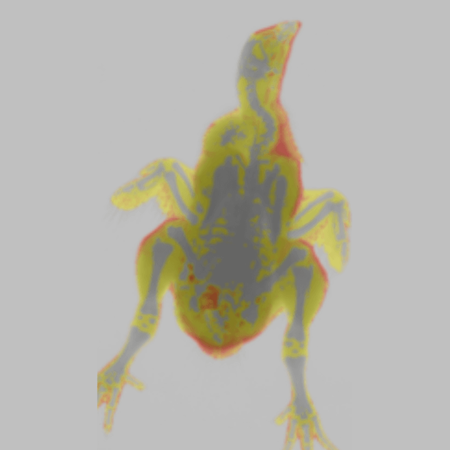

Color Image - Rat. Image Credit: Scintica Instrumentation Inc

Chicken Color Image. Image Credit: Scintica Instrumentation Inc